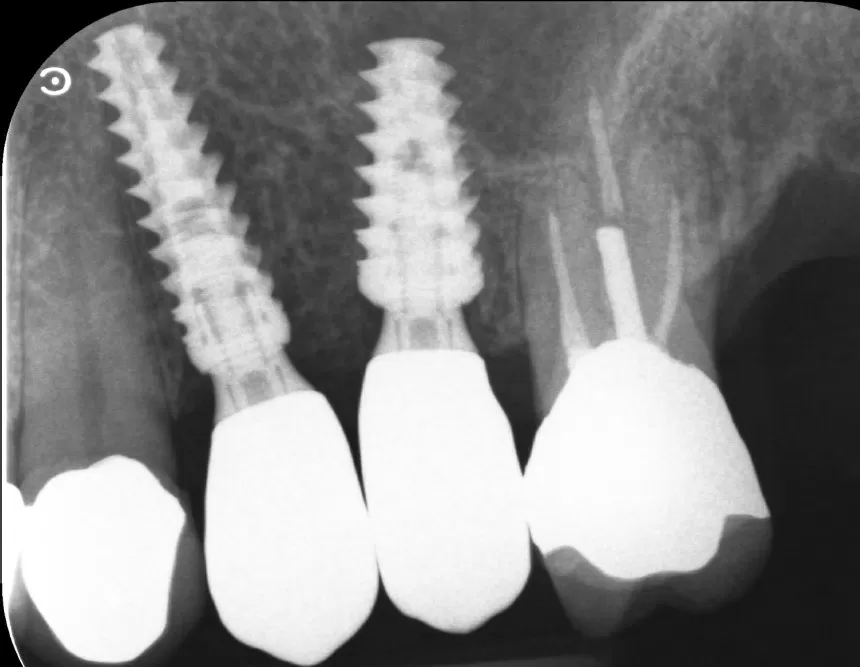

Caso clinico di carico immediato su rialzo crestale del seno mascellare con tecnica a espansori.

Orrori Evitabili: Impianti, Connessioni, e Componenti

Errori evitabili nella scelta e nel posizionamento di impianti, connessioni protesiche e componenti intermedie.